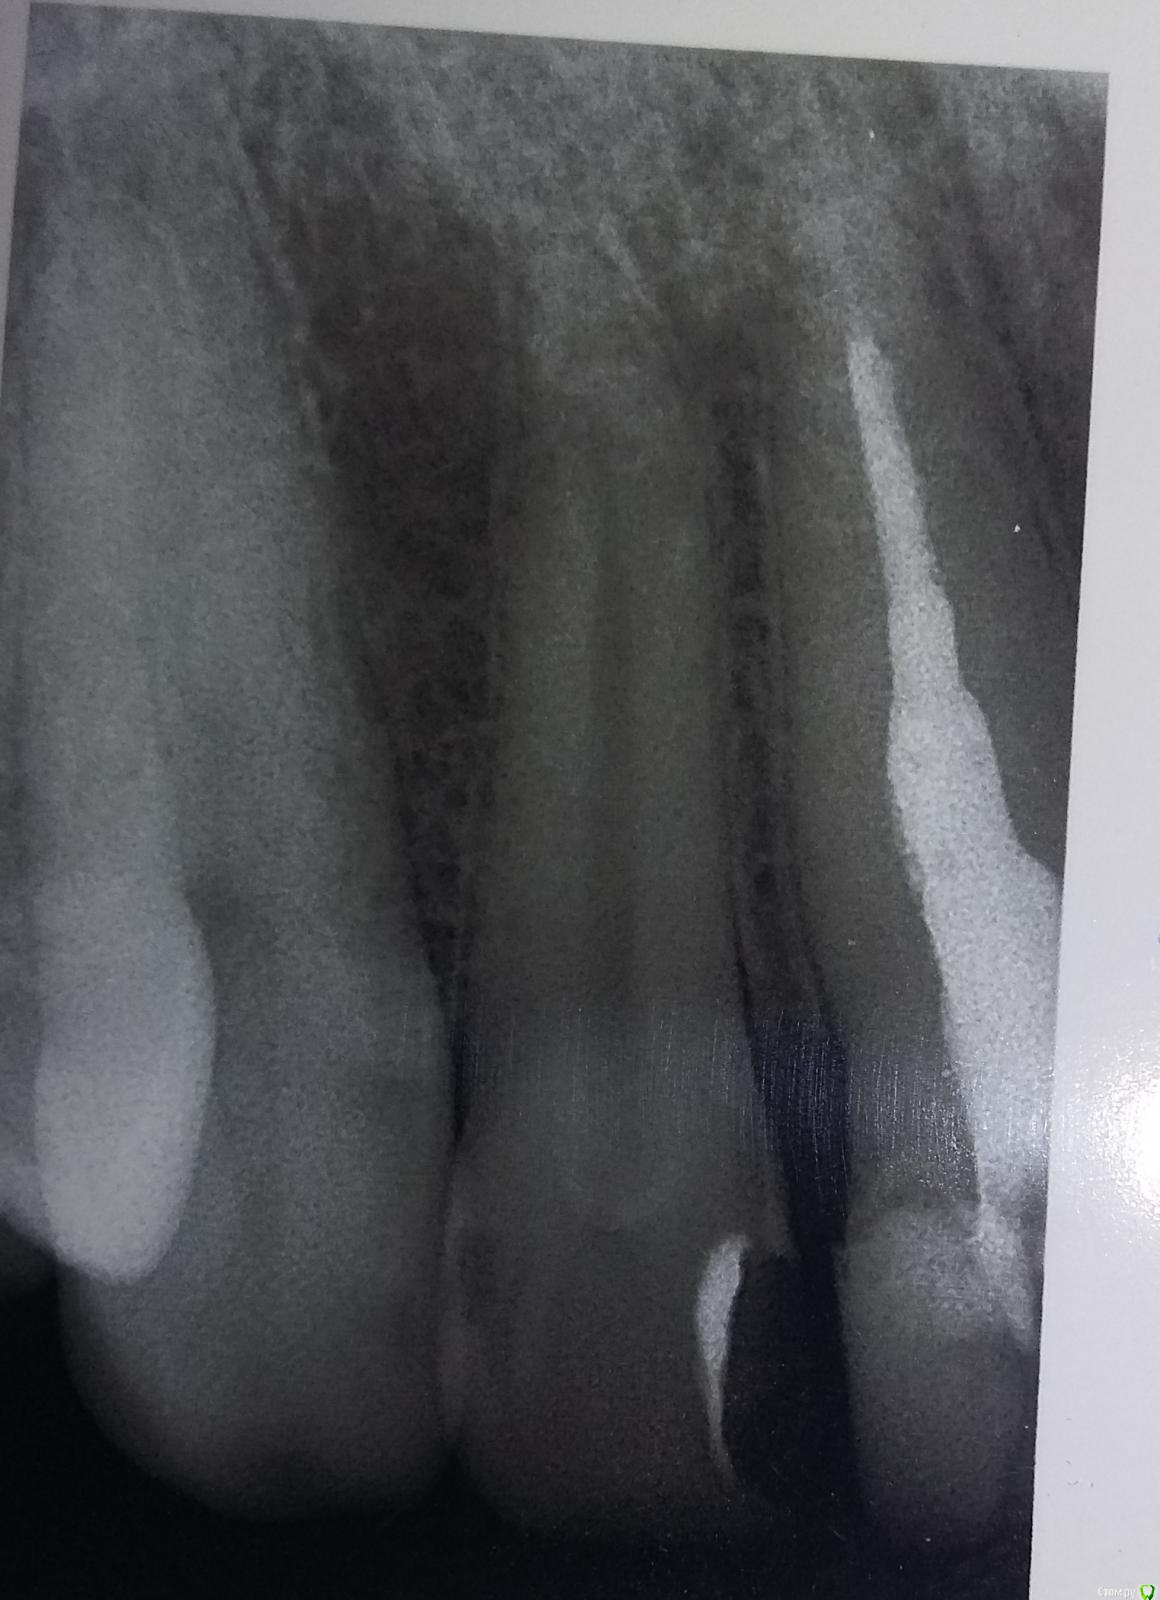

Ирина. Опубликовано 18 августа, 2015 Автор Поделиться Опубликовано 18 августа, 2015 Коффердам не использовали точно. Перелечивали в 2 этапа. 1 день распломбировка.Второй - перепломбировка. Перепломбировка длилась около получаса. В процессе и по завершению много раз делались снимки (раза 4-5).Чем запломбировали канал, к сожалению, не знаю. Но клиника престижная, не думаю, что чем-то устаревшим. Дело в том, что в клинике со 100% уверенностью утверждают,что канал пройден до конца,гарантированно заверяют,что никогда не будет ни кисты, ни гранулемы, пустоты нет. Показывают мне какую-то тоненькую ниточку пломбировочного материала в апикальной части.Но почему-то ее вообще не видят другие врачи.Я уже и не знаю, кому верить. Ссылка на комментарий

Ирина. Опубликовано 18 августа, 2015 Автор Поделиться Опубликовано 18 августа, 2015 Сегодня пломбировали соседнюю двойку. Вот там даже я вижу своим непрофессиональным взглядом,что канал пройден до конца. В единице не вижу Ссылка на комментарий

St. Опубликовано 18 августа, 2015 Поделиться Опубликовано 18 августа, 2015 (изменено) там вроде видна слабая тень материала. Мне кажется, не стоит пока трогать этот зуб. Просто через 6 и 12 мес повторить прицельные снимки. 100% при лечении каналов не бывает в принципе, может быть например 99.. потому что прогноз зависит не только от доктора , а в том числе и от вашего организма, на который мы не всегда можем повлиять. Изменено 18 августа, 2015 пользователем St. 1 Ссылка на комментарий